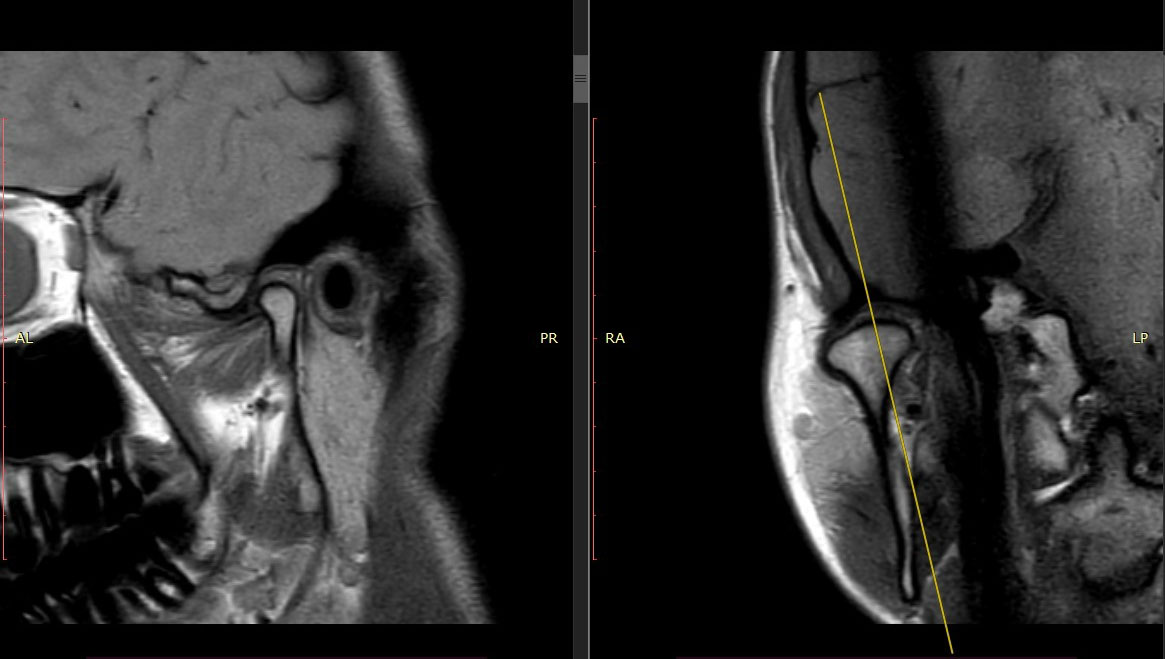

МРТ височно-нижнечелюстного сустава (ВНЧС)

МРТ височно-нижнечелюстного сустава показывает состояние не только сочленения костей, но и мягких тканей лица. На снимках видны малейшие изменения в хрящах, мышцах, челюстных костях и даже сосудах.

При МРТ ВНЧС с функциональными пробами делают отдельные снимки пациента с открытым и закрытым ртом. Также врач может попросить открывать и закрывать рот во время сканирования. Такой способ помогает оценить функциональность нижней челюсти и выяснить, что мешает ее нормальной работе.